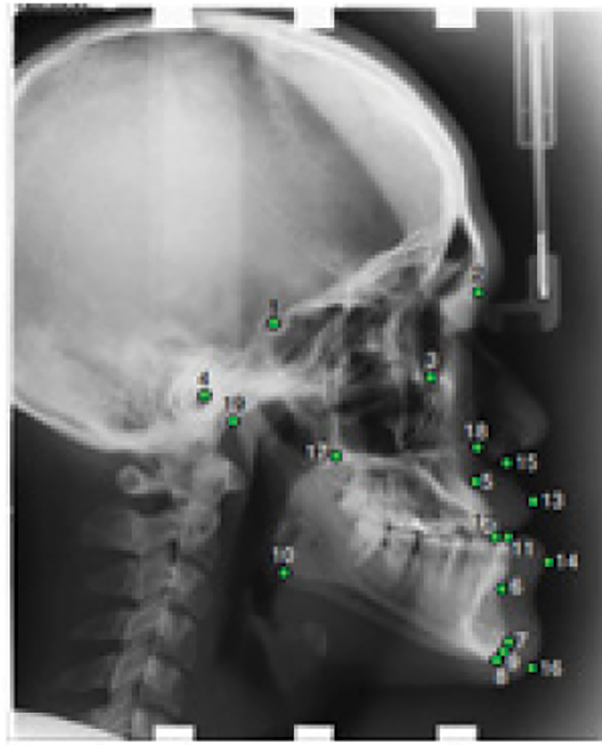

In this work, we used the public X-ray dataset proposed at the International Symposium on Biomedical Imaging on cephalometry landmark detection challenge ISBI2015 [15] and ISBI2019 [13]. The X-Ray images are lateral cephalograms acquired from 400 patients including 235 females and 165 males. The sample ranged between 7–76 years in age with a mean age of 27 years. Each image contains 19 landmarks manually marked by two clinical orthodontists as shown in Fig. 1. The landmarks were chosen based on the common structures used in cephalometric evaluations such as Wits Appraisal. The training set consists of 150 images while Test1 and Test2 datasets are made up of 150 and 100 images, respectively, in TIFF format. The image resolution is 1935 × 2400 pixels and the spatial resolution is about 0.1 mm.

Figure 1: Cephalogram annotation showing the 19 landmarks